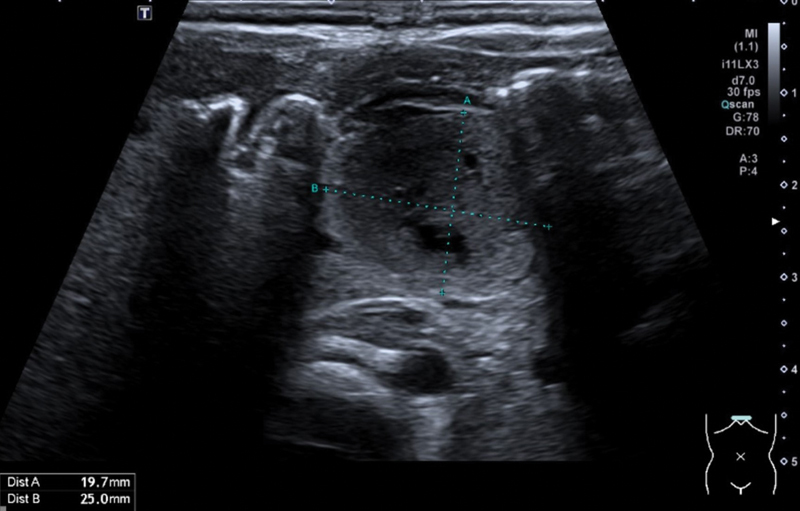

Accessory liver lobes are rare. We present the rare case of torsion of an accessory liver lobe in a neonate. A 13-day-old newborn presented with failure to thrive and hematemesis without fever. The initial workup with sonography, magnetic resonance imaging, and upper gastrointestinal study was suspicious of a duplication cyst, most likely in the posterior wall of the stomach. Laboratory and radiological findings were not suggesting a choledochal cyst. We performed a laparotomy with resection of the 3.2 × 2.1 × 1.1 cm mass. Intraoperatively, the cystic formation extended from of the liver bed up to the lesser curvature of the stomach. The mass was attached to the left liver lobe with fibrous bands. Histopathology revealed necrotic liver parenchyma with patent viable biliary ducts, indicative of an accessory liver lobe that underwent torsion in the perinatal period. The postoperative course and follow-up (6 months so far) were uneventful. To our knowledge, this is the youngest described patient in the literature with an accessory liver lobe torsion and the second case report concerning this entity in a neonate. It presents an extremely rare differential diagnosis in symptomatic neonates with a cystic mass in the upper abdomen.